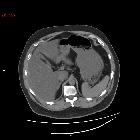

medical management of emphysematous gastritis with concomitant portal venous air: a case report. CT of the abdomen showing air in the stomach wall and portal venous system. Black arrow: Portal venous air. White arrows: Air in the stomach wall.